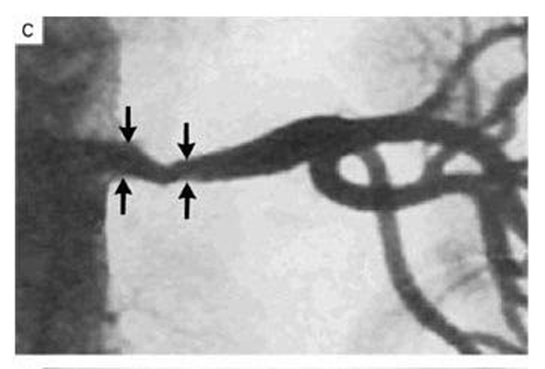

Renal arter stenozu araştırması yüksek tansiyon hastası kişilerde yapılmalı ve gerekli durumlarda tedavi edilmelidir. Renal arter stenozu hastalığının tanısında tümüyle radyoloji görüntüleme yöntemleri kullanılıp doppler ultrasonografi ve MR ya da bilgisayarlı anjiyografiler kullanılır.

Her renal arter stenozu (böbrek damar daralması) tedavi yapılmasını gerektirmez. Tedavi olarak anjiografi sonrası tıkalı damara ince bir kateterle girilerek pıhtı eritici tedavi yapılır. Sonraları bir darlık görülürse, balon ya da stent uygulanır. Bu tedavilerden istenilen sonuç alınamadığı taktirde, cerrahi tedavilere başvurulur.